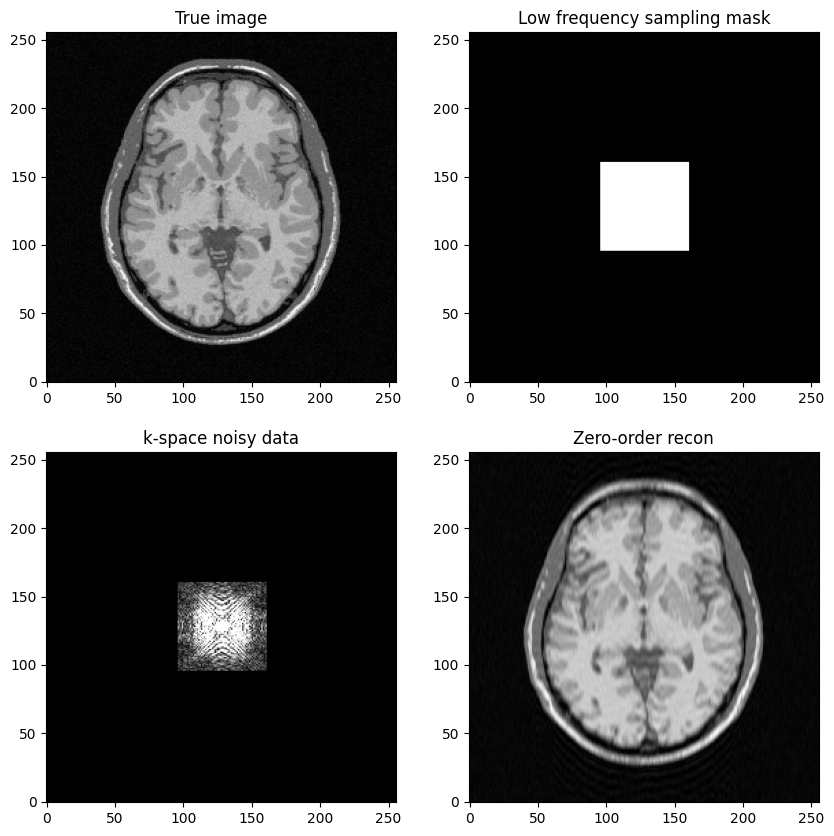

a low-frequency Cartesian mask is defined by a square box in k-space centered at .

Question: based on the previous example, try to construct a low-freqency sampling mask defined by a square box centered around .

Then, replicate the same steps:

Generate noisy masked data

Perform zero-filled MR image reconstruction

Visualize results and study the impact of both the noise level and the mask size

fig, axs = plt.subplots(2, 2, figsize=(10, 10))

axs[0, 0].imshow(mri_img)

axs[0, 0].set_title("True image")

axs[0, 1].imshow(kspace_maskbox)

axs[0, 1].set_title("Low frequency sampling mask")

axs[1, 0].imshow(np.abs(kspace_data), vmax=0.01*np.abs(kspace_data).max())

axs[1, 0].set_title("k-space noisy data")

axs[1, 1].imshow(np.abs(image_rec0))

axs[1, 1].set_title("Zero-order recon")

plt.show()